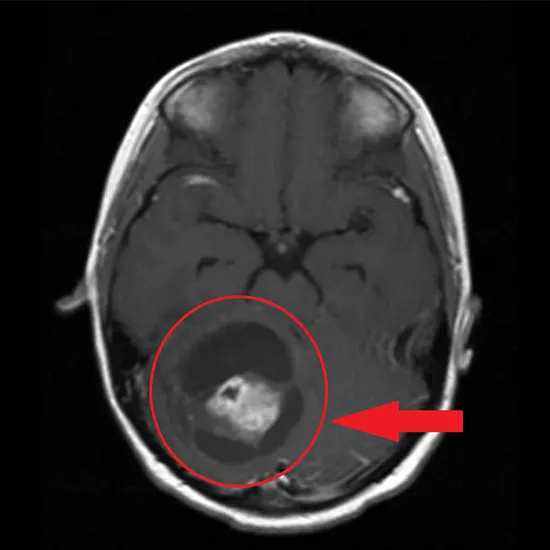

Astrocytoma is a type of brain tumor that arises from astrocytes, which are a type of glial cell that provides support and nourishment to nerve cells in the brain. Astrocytomas are the most common type of glioma, which is a type of tumor that originates from glial cells in the brain.

Diagnosis is typically confirmed through imaging studies such as MRI (magnetic resonance imaging) of the brain, and a biopsy may be performed to determine the exact type and grade of the astrocytoma.